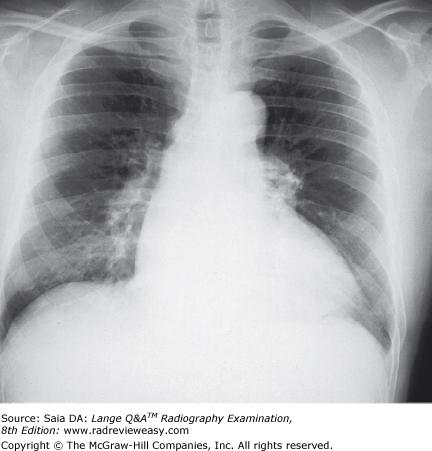

The PA chest radiograph shown in the figure below demonstrates

1. rotation

2. scapula superimposed on lung fields

3.

adequate inspiration

1, 2, and 3

The figure below demonstrates which of the following conditions?

dextrocardia

The PA chest image shown in Figure 4–13 exhibits which of the following qualities?

- Adequate penetration of the heart

- Long-scale contrast

- Adequate inspiration

The figure below illustrates a sectional image of the abdomen. Which of the following is represented by the number 13?